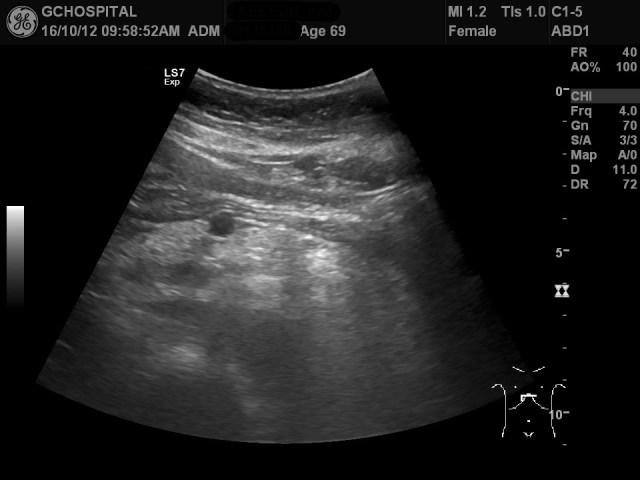

71세여자환자의 복부초음파영상입니다. 췌장의 머리와 몸통 사이쪽에 약 1.4센티미터 크기의 낭종이 있으며, 예전부터 이 낭종을 계속 추적관찰해오셨습니다.

계속된 추적관찰 과정에서 앞서 보였던 단순낭종 외에 췌장 내에 별다른 병변은 보이지 않았습니다. 위 영상에서 췌장의 몸통과 꼬리부분이 잘 보이고 있습니다.